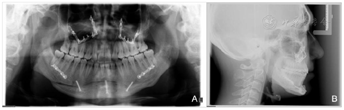

曲面断层片检查(图3-A):B1、B3间骨量不足,牙根远中倾斜,第三磨牙阻生。

头颅侧位片检查(图3-B)表1:ANB-4.5,骨性三类反合。